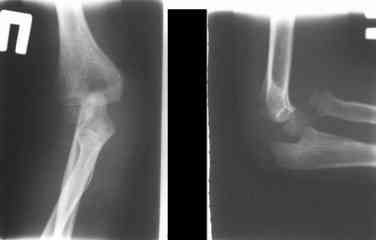

1 подвывих головки лучевой кости в положении супинации - через 2 недели после операции- под ЭОП: аппарат разблокирован, повторное вправление головки, стабилизация аппарата.

2 По снятии аппарата через 2 мес после операции рефрактура в месте остеотомии(на фоне активного ротационного движения)- под контролем ЭОП выполнен

интрамедуллярный остеосинтез TEN. Положение головки луча стабильное.